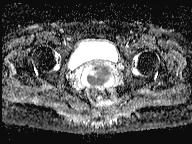

轴位

T2加权像

可见局部晚期浸润性内生型宫颈癌,肿瘤大小为30 x 32 x 48 mm。该肿瘤已侵犯宫颈前唇和后唇的深层间质,以及子宫肌层的下段。

此外,肿瘤还累及宫旁组织。影像学检查发现异常淋巴结肿大,最大短轴直径(SAD)为10 mm,位于髂总血管分叉处和髂内动脉链下方。该淋巴结肿大在弥散加权成像(DWI)上显示水限制,且增强扫描后可见强化。